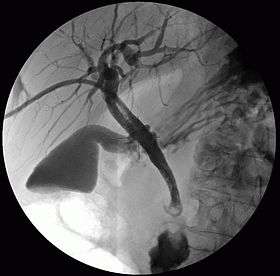

Cholangiography

Cholangiography is the imaging of the bile duct (also known as the biliary tree) by x-rays. There are at least two kinds of cholangiography:

- percutaneous transhepatic cholangiography (PTC): Examination of liver and bile ducts by x-rays. This is accomplished by the insertion of a thin needle into the liver carrying a contrast medium to help to see blockage in liver and bile ducts.

In both cases fluorescent fluids are used to create contrasts that make the diagnosis possible. Cholangiography has largely replaced the previously used method of intravenous cholangiography (IVC).